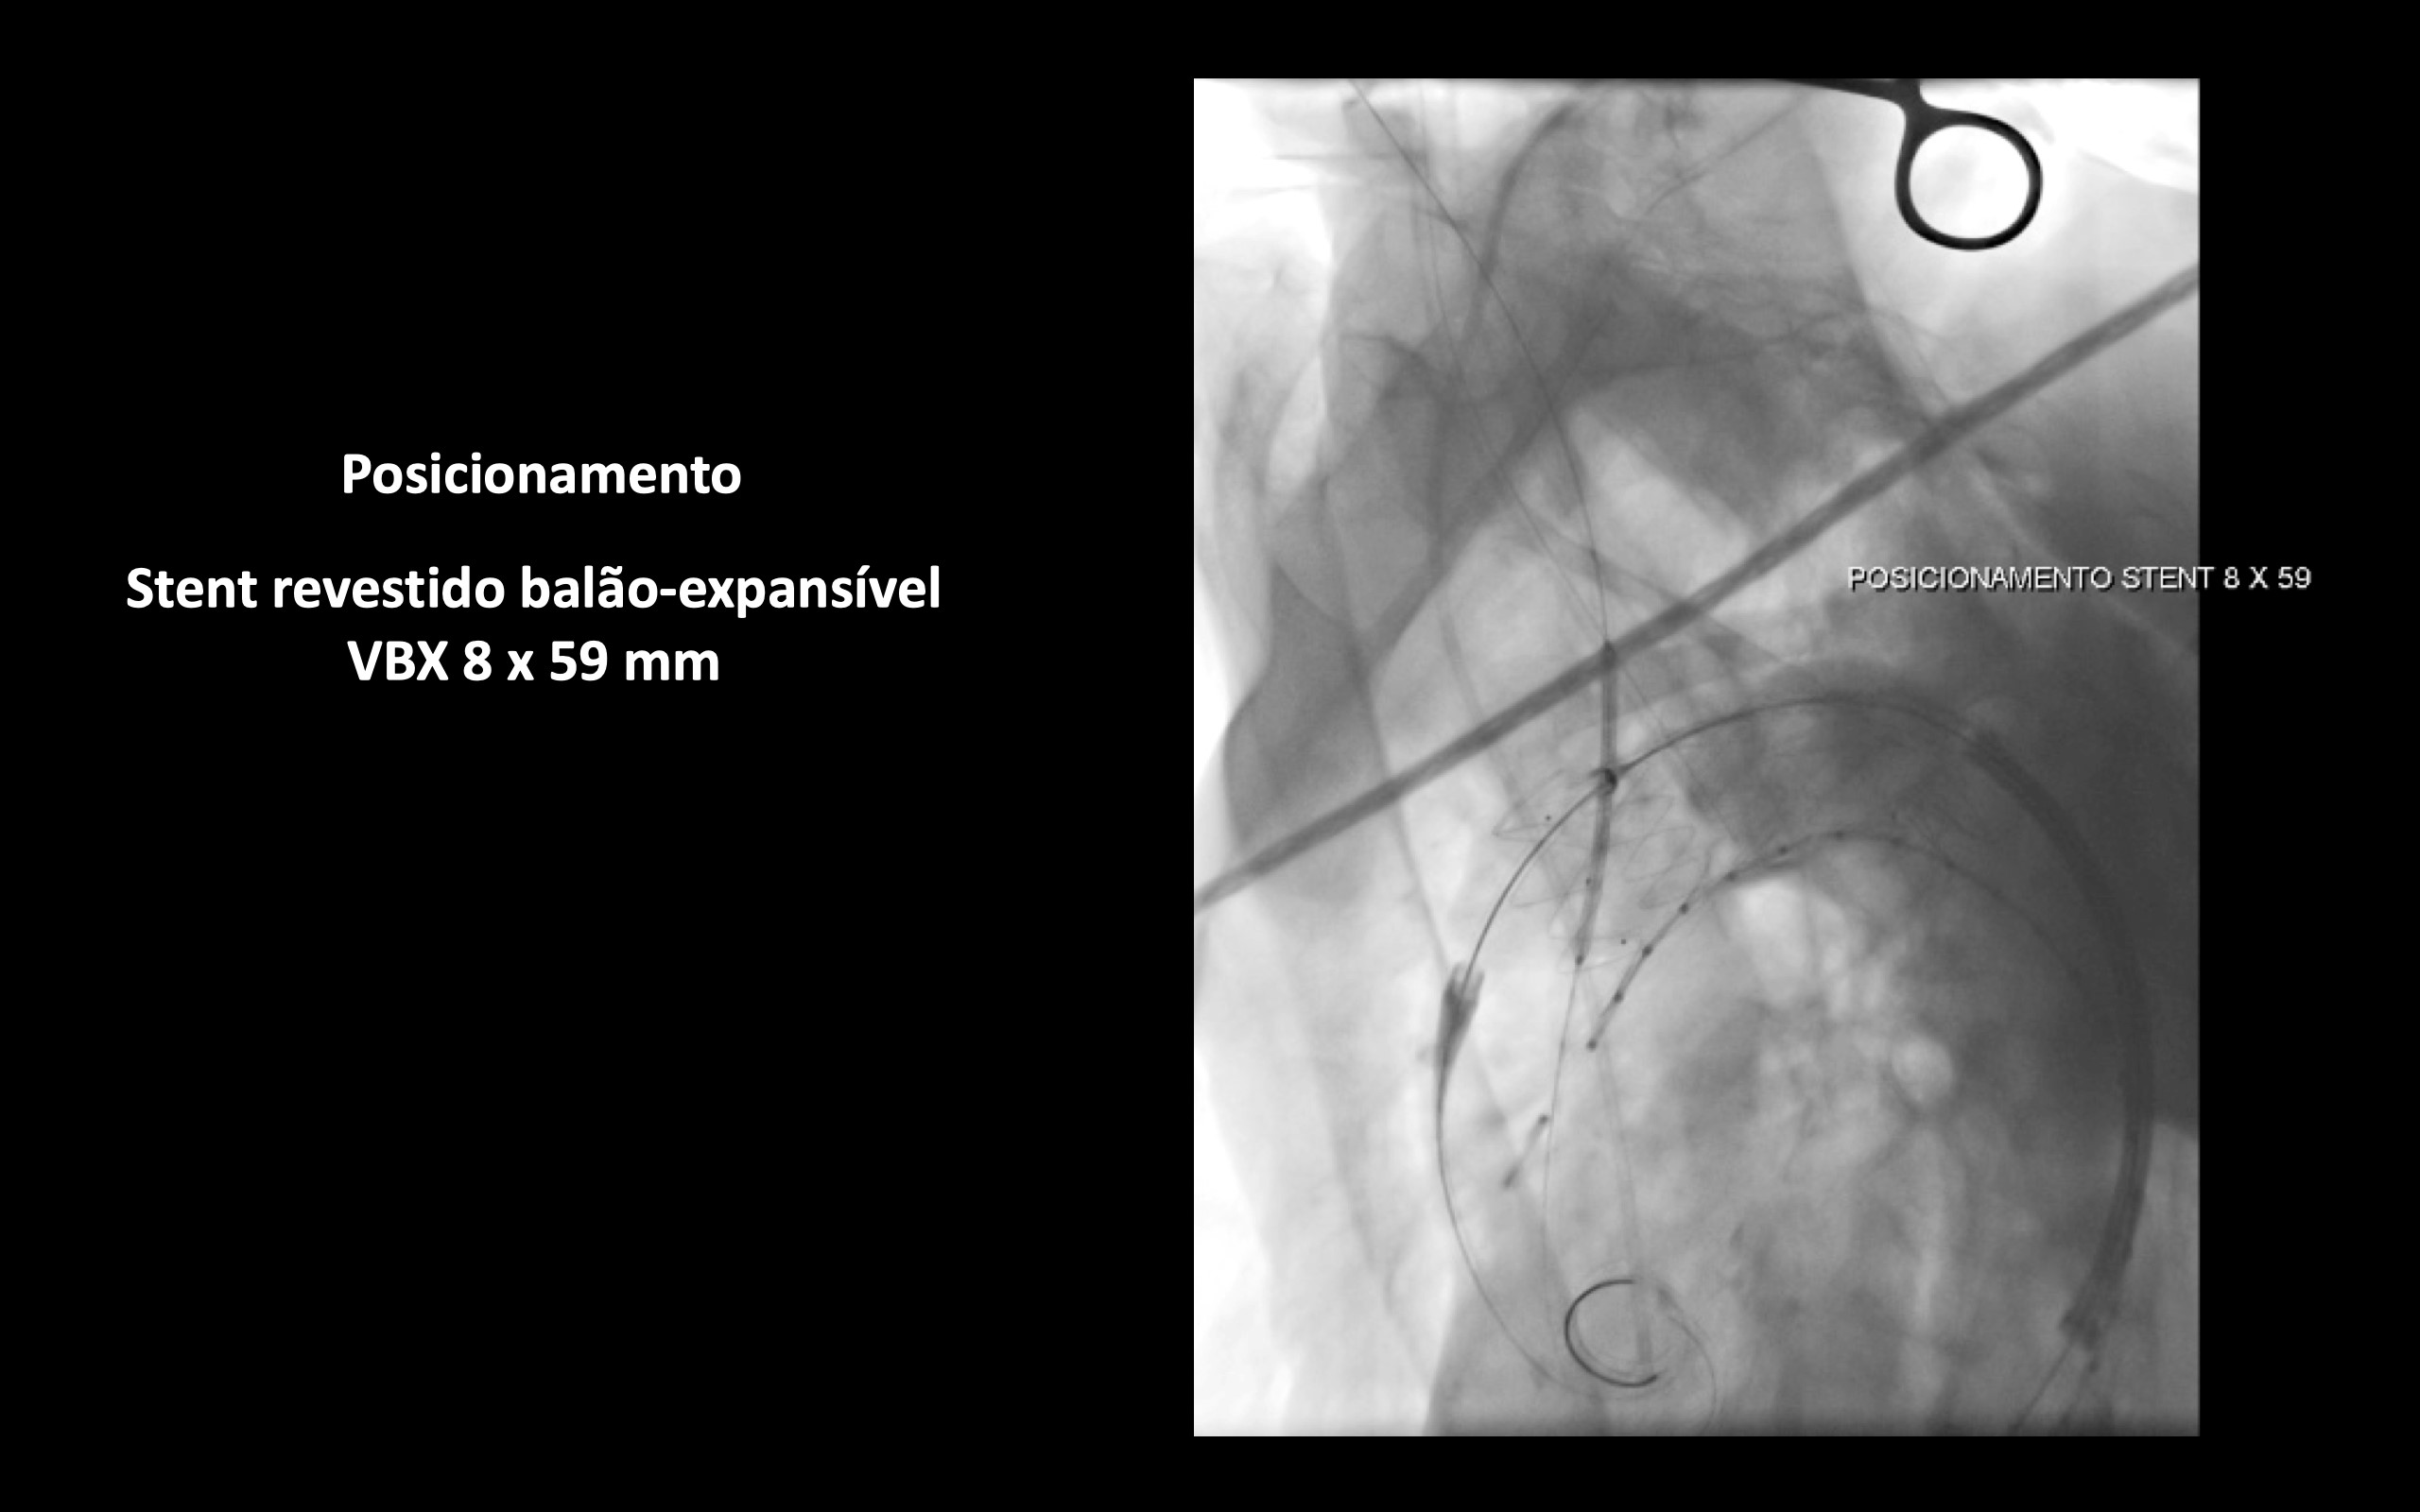

Optado por tratamento endovascular (TVAR) e técnica de chaminé.